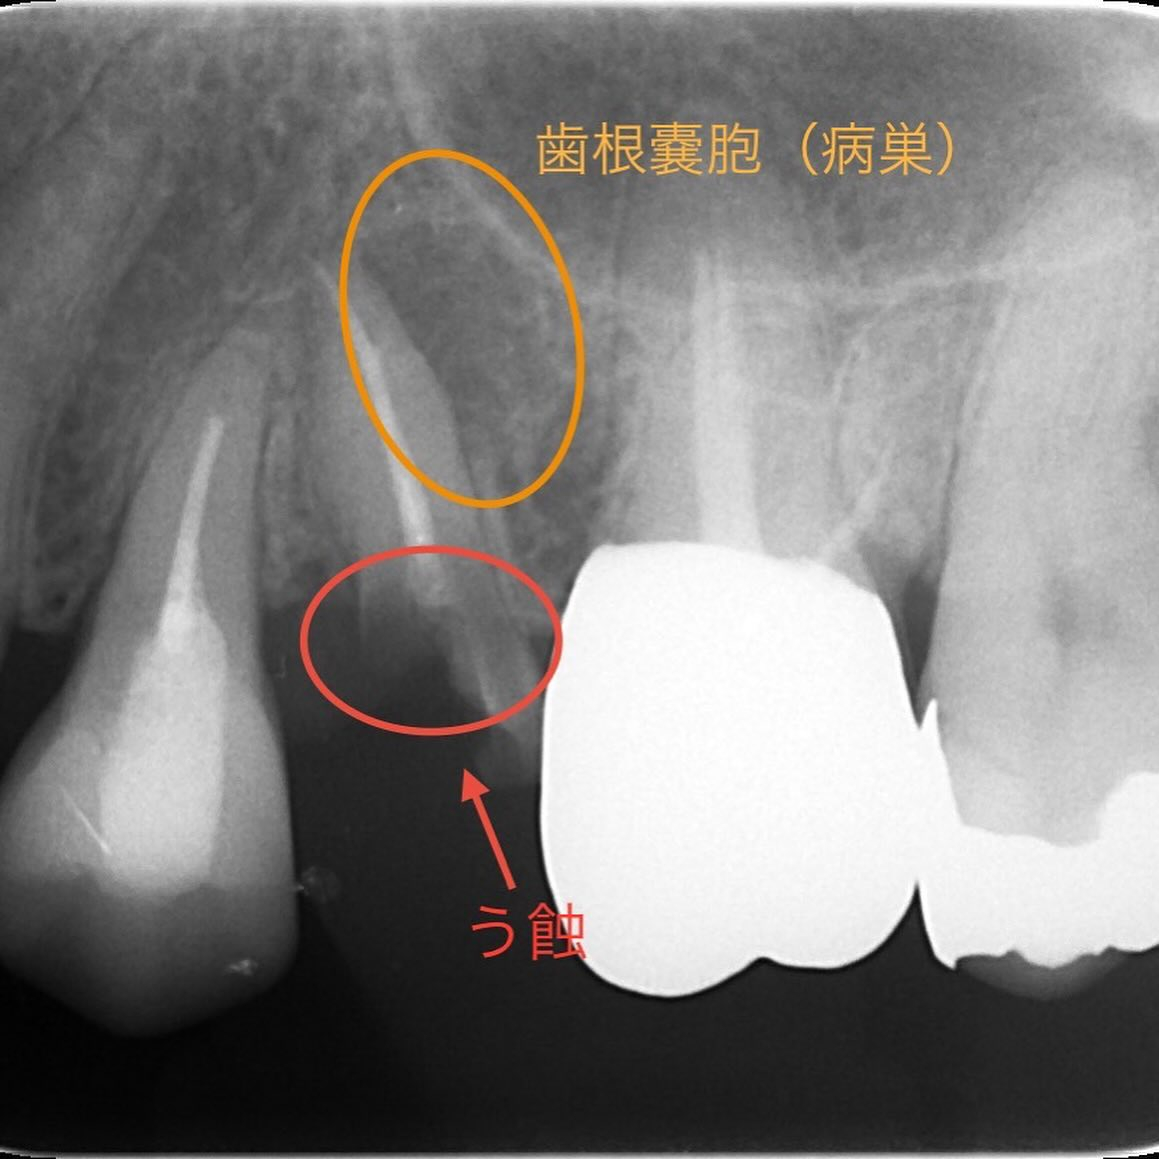

レントゲン写真を見て頂くと、歯根の先端付近に黒い影がありますよね(オレンジの〇)🔎

これは歯根嚢胞と言う病巣で、この病巣が原因で歯を支える骨が吸収していました。

この嚢胞の大きさから、破折が起きている可能性も予想されます。

また、赤〇で囲んだ所は虫歯になっており歯の頭の部分が欠損している状態でした🥲

歯肉の内部深くに虫歯が進行しておりそもそも虫歯を取りきることが出来ない事、嚢胞の存在から補綴治療(歯の被せ物)に進んでも予後が悪いと判断しました✍️

抜歯した歯には破折線もあり、レントゲン写真ではハッキリとは写ってませんでしたが破折が原因で歯根嚢胞が生じていた可能性があります🧐